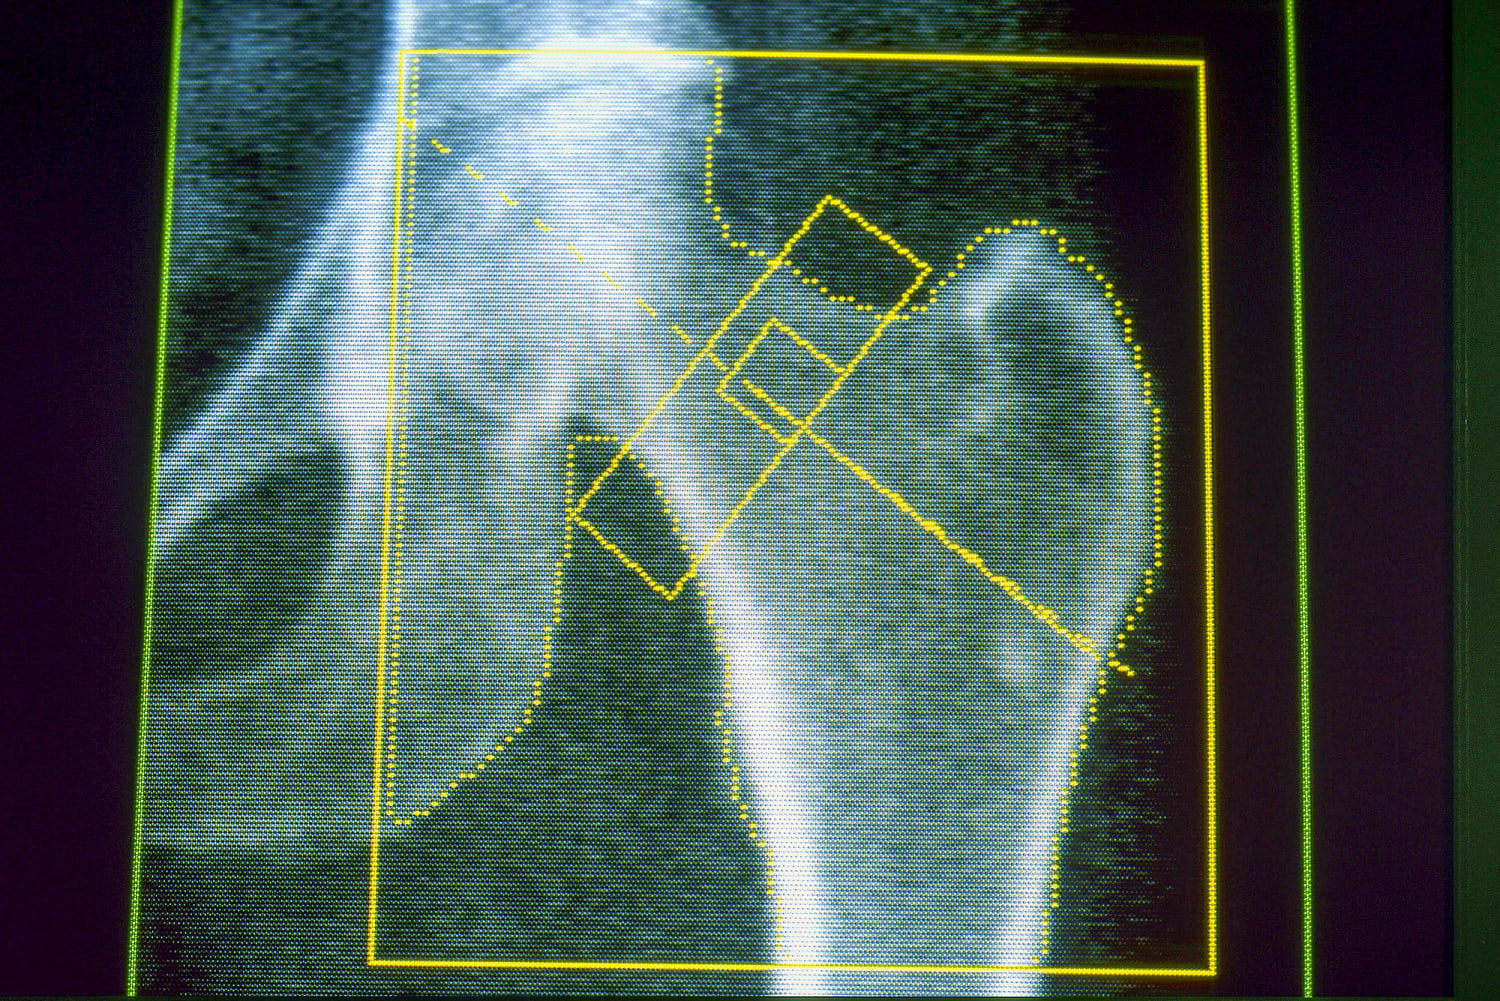

Osteoporosis is a disease that weakens the bones and makes them likelier to break or fracture, often from minor falls. It’s a common concern for many older adults and for people who lose a significant amount of weight over a short period of time. Gout, meanwhile, is a painful form of arthritis that can occur when the body has too much uric acid, which can come from a diet high in red meat and alcohol — as well as rapid weight loss.

About 4% of GLP-1 users developed osteoporosis, compared with a little over 3% of nonusers — an increased risk of about 30%. A related condition, osteomalacia, which involves the softening of the bones, was rare but also occurred about twice as often among people on GLP-1s.

Because the new research was observational, it can’t prove the medications caused either condition. Horneff said the team didn’t know about patients’ diet or exercise habits, or whether they were taking vitamin D supplements or other nutrients important for bone health. But the results echo other research, including a study published in February in the Journal of Clinical Endocrinology & Metabolism that linked GLP-1 drugs to a higher risk of osteoporosis-related fractures in older adults with Type 2 diabetes.